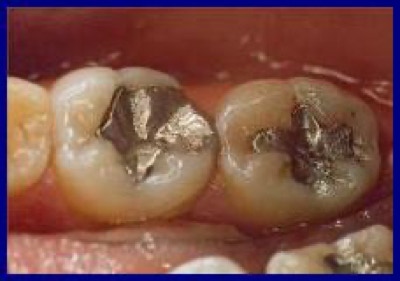

Keramikinlays

Der Gesichtspunkt der Ästhetik hat in den Zahnarztpraxen während der letzten Jahre rapide an Bedeutung gewonnen. Immer mehr Patienten wünschen heute eine "kosmetisch ansprechende" Füllung auch im Seitenzahnbereich. Keramikinlays sind zweifellos die ästhetisch allerschönste Alternative zum Amalgam.

VORHER

NACHHER